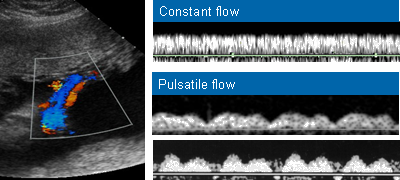

Diagnóstico ultrassonográfico:

- Cisto anecóico supra-tentorial em linha média, alongado com fluxo arteriovenoso ativo demonstrado pelo color Doppler.

- O defeito se desenvolve no início do primeiro trimestre, mas o aneurisma só se torna aparente à ultrassonografia no terceiro trimestre.

- Em 90% dos casos há insuficiência cardíaca de alto débito e hidropsia secundária.